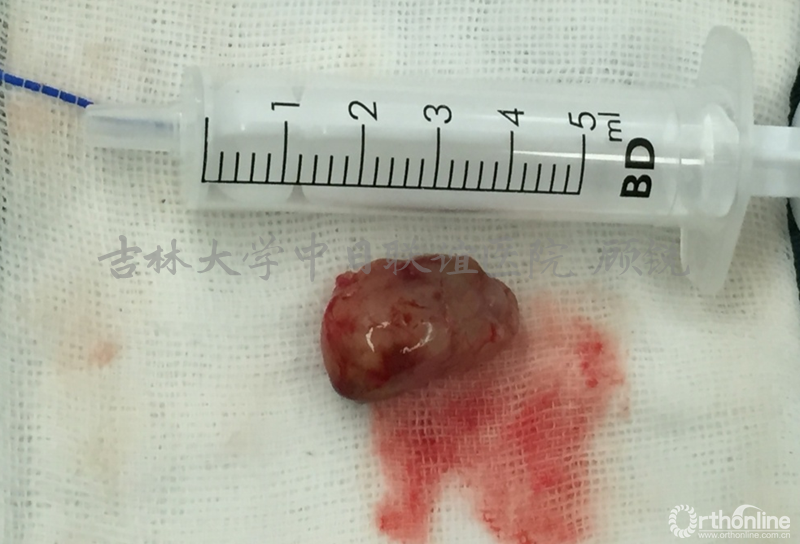

肿瘤外像:

术后病理: